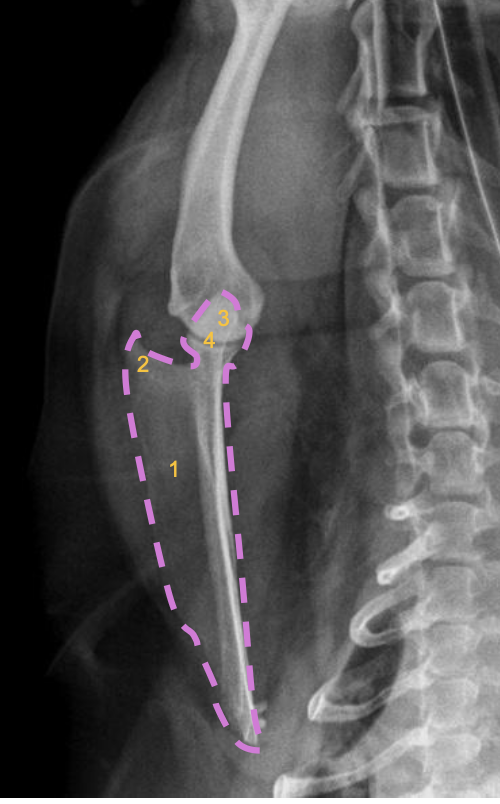

what radiographic view of the humerus is shown?

caudo-cranial view